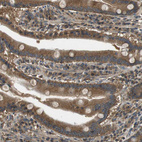

Immunohistochemical staining of human bone marrow shows strong cytoplasmic positivity in hematopoietic cells.